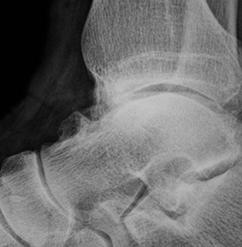

En la Rx lateral se detectan los osteofitos en forma de pico de pájaro, en la parte anterior de la articulación tibiotalar (15, 16). (Fig 89).

Fig 89. Pinzamiento anterior.

Rx lateral. Formación de osteofitos en la parte anterior de la tibia y el borde superior del talo.